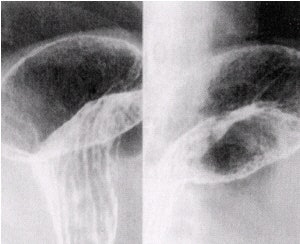

![]() |

| Images of the duodenal bulb in four slightly different views (10 x 12 image receptor, 4 on 1). Image courtesy of Dr. Naveed Ahmad. |

- With the tabletop horizontal and patient in right lateral position, image the duodenal bulb. Visualize the barium-filled duodenal bulb and obtain at least four slightly different views. If the bulb is not well seen, have the patient inhale deeply and stop breathing briefly to improve visualization of the bulb. Alternatively, the patient can be placed prone and the duodenal bulb can be compressed from underneath by using a balloon compression paddle.